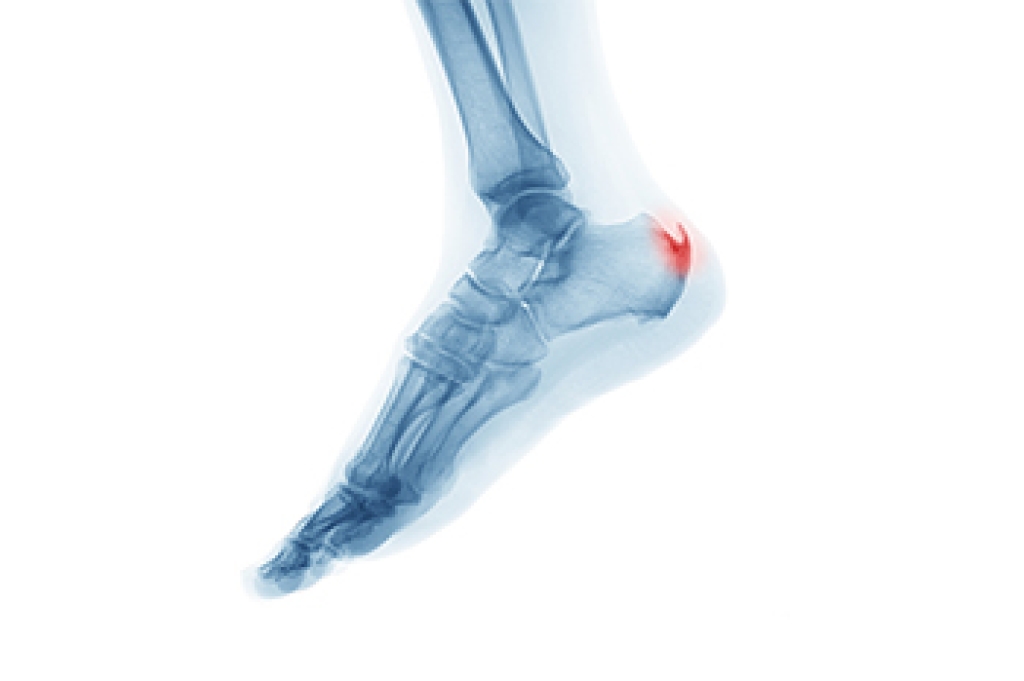

- Achilles Tendon – May shorten and stiffen with prolonged wear

- Plantar Fasciitis